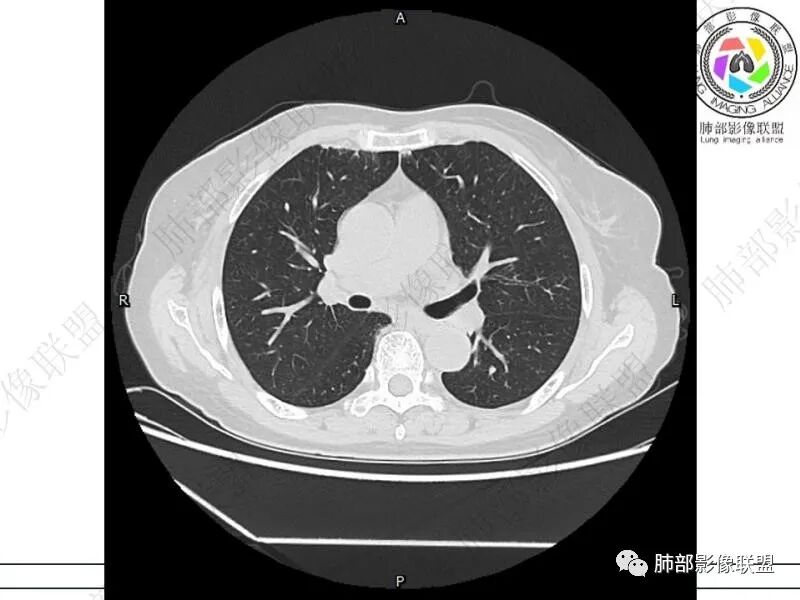

谢加平:结肠癌术后史,两肺胸膜下多发结节及斑块实变病灶,实边边界平直征(亚急性和慢性病变过程),双肺下叶后基底段胸膜下为甚,与胸膜平行特点,见支气管充气征,边缘模糊的GG0,首诊2022年11月18日肺部CT,与治疗11月28日对比,病灶未吸收,双肺下叶胸膜下病灶有侧向融合特点,综合分析符合炎性肉芽肿,隐球菌感染。

老年女性,结肠癌术后。两下肺胸膜下为主片状实变,右下肺短期复查融合且病灶长轴平行于胸膜,实变内可见支气管充气征,边缘磨玻璃晕,另两肺内胸膜下散在数枚小结节状、楔形实性灶。考虑感染性病变,隐球菌可能,鉴别肺转移。

THINKER:胸膜下实变,常见OP丶PC丶PE丶腺癌丶腺病毒丶非典型病原体。1.此例肠癌,免疫妥协人群,PC要考虑,但荚膜抗原阴性,阴性预测值很高。2.肿瘤史,本身易高凝状态,肺栓塞要考虑。3.OP  胸膜下实变,经典型OP影像。故:PE>OP>PC

IgG4确实符合,强烈的纤维化;最大的病灶无坏死

2.影像特征:双肺胸膜下多发实性结节、磨玻璃影及实变影,胸膜下优势分布、晕征、胸膜下脂肪间隙存在,部分病灶边界平直征,有侧向融合趋势。